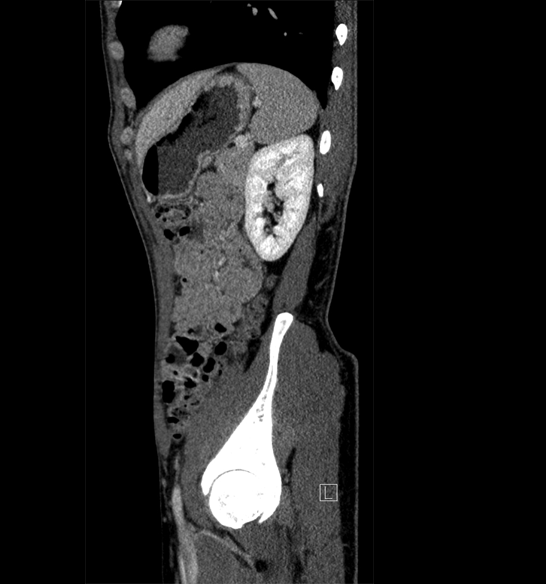

Body

Covers abdominal CT anatomy.